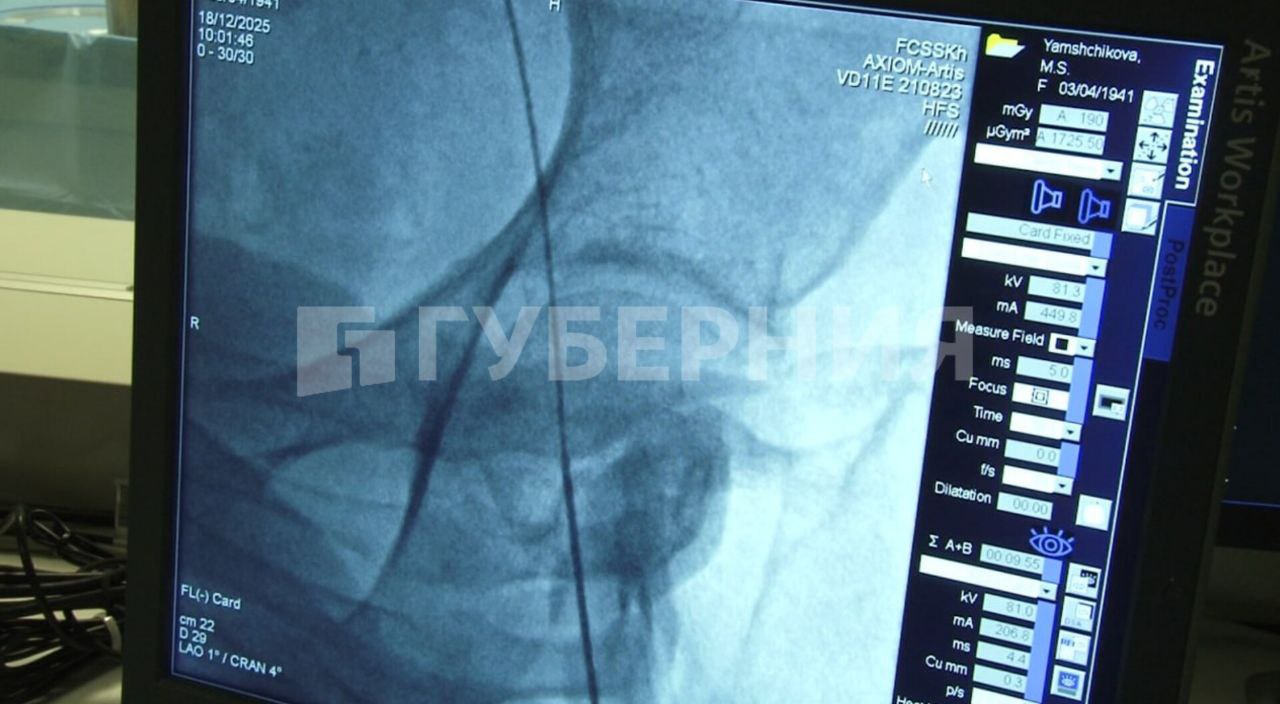

Губерния l Хабаровск

Хабаровские хирурги применяют новую технологию при операциях на сердце Она позволяет снизить риск инсультов после подобных вмешательств что особенно актуально для возрастных пациентов Во время операции хирурги вводят катетер который содержит в себе две ловушки Они позволяют частично перекрывать кровоток по артериям мозга Таким образом объясняют специалисты операция становится более безопасной То есть фильтруется та часть которая потенциально может вызывать инсульты и слабоумие так называемую деменцию Это мелкие частицы которые ловушка позволяет задержать во время операции не давая проникнуть в головной мозг и нарушить его питание рассказал заведующий отделением рентген хирургии федерального центра сердечно сосудистой хирургии Хабаровска Константин Поляков Обучение этому методу ведущие хирурги страны проходили за рубежом и поделились опытом со специалистами хабаровского сердечно сосудистого центра С использованием новой технологии уже прооперировано более 60 пациентов Самому пожилому из них 92 года В дальнейшем эту программу планируют развивать